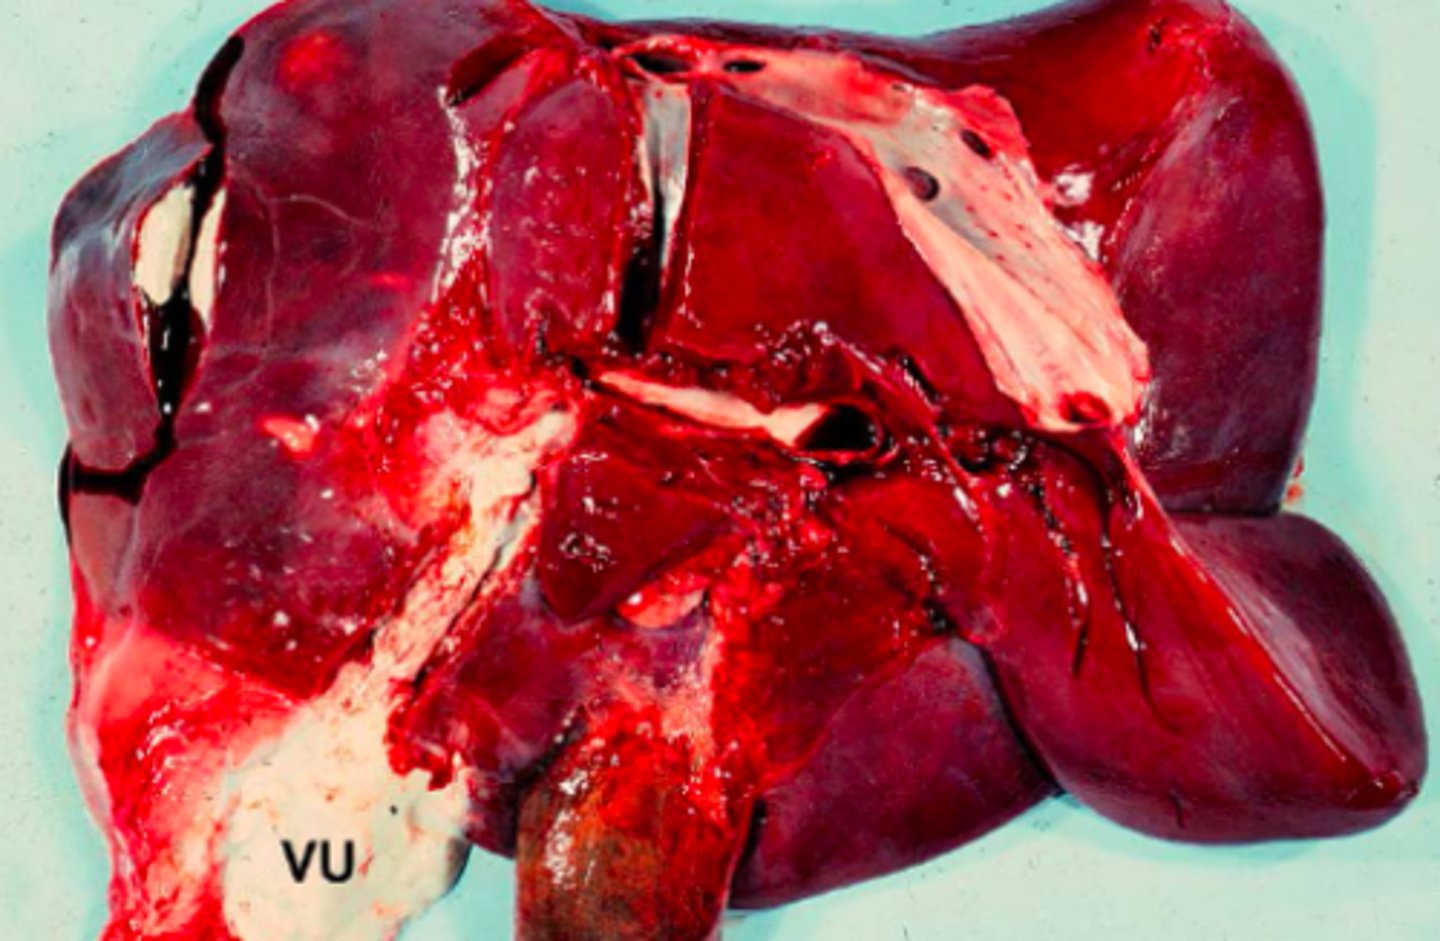

Lever fra okse, hvad er den patoanatomiske diagnose?

Lever fra okse, hvad er den patoanatomiske diagnose?

Lever fra okse, hvad er den patoanatomiske diagnose?

Akut, hæmorrhagisk og nekrotiserende hepatitis.

Ætiologi: infektion med Fasciola heptatica

Lever fra får, hvad er den patoanatomiske diagnose og ætiologien?

Lever fra får (med diaphragma, D), hvad er den patoanatomiske diagnose og ætiologien?